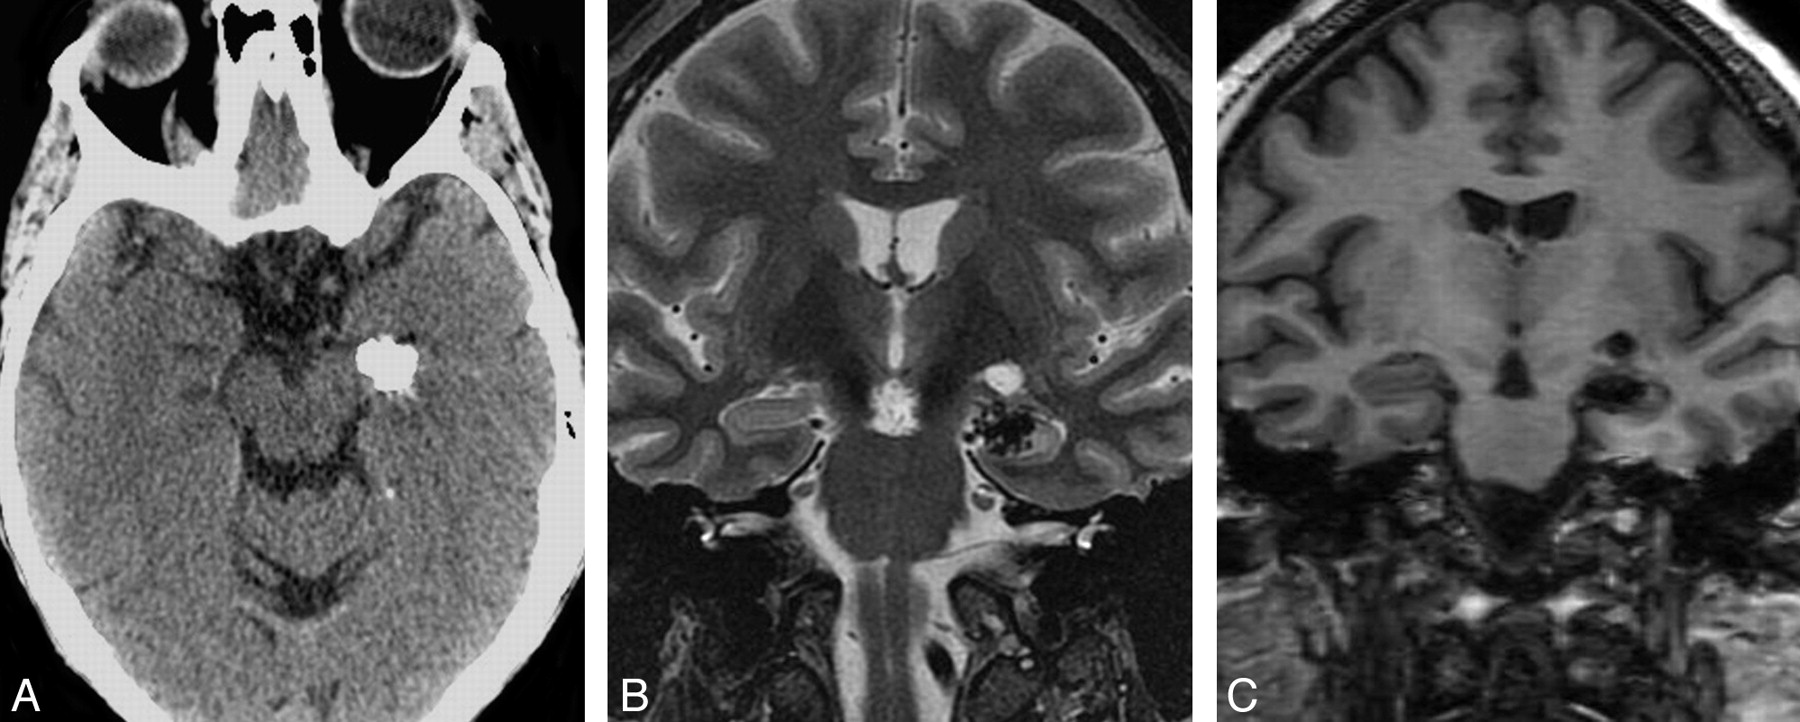

The first case, an incidentally found lesion, was a 3.2-cm extra-axial intraventricular mass (Figure 1). The remaining 3 patients with a history of seizures had intra-axial brain masses, ranging in size from 1 cm to 1.8 cm, located in the right parietal lobe near the postcentral gyrus, in the left hippocampus (Fig 2), and in the right temporal lobe, respectively. Preoperatively, the intra-axial temporal lobe lesions mimicked cavernous malformations or densely calcified neoplasms such as oligodendroglioma or ganglioglioma on the basis of their CT and MR imaging appearance. The intraventricular mass mimicked a meningioma but prospectively was thought to represent a pseudoneoplasm because of the lack of enhancement. The right parietal lesion had previously been resected 18 years previously, with a “benign” pathologic appearance and no specific diagnosis.

Typical radiologic features of extra-axial CAPNON. A, Noncontrast CT scan shows a densely calcified mass in the right temporal horn. B, Axial T2-weighted MR image shows a uniform T2 hypointense mass centered in the right temporal horn. C, Axial T1-weighted postgadolinium sequence illustrates marked T1 hypointensity with scattered linear areas of enhancement that correspond to the strands of T2 hyperintensity. This appearance was seen in both of our larger lesions and may correspond to the vascular stromal elements seen within these lesions.

Important differential considerations for intra-axial calcified masses include calcifying neoplasms such as ganglioglioma and oligodendroglioma, vascular lesions such as cavernous malformation, and infections such as tuberculosis. Intraventricular masses can also raise the possibility of choroid plexus tumors, meningioma, or ependymal tumors. Our small series suggests that important MR imaging features may allow the radiologist to suggest CAPNON in the differential diagnosis. CT images of CAPNON typically show solid attenuated calcifications, and the MR imaging often shows a well-defined lesion that is uniformly hypointense on both T1- and T2-weighted images without surrounding edema. In our cases, only minimal linear internal or rim enhancement was present. The larger lesions (cases 1 and 2) best demonstrated the more serpiginous internal enhancement, which has been hypothesized to represent the vascular or stromal characteristic of these lesions (Fig 1).6 None of our cases demonstrated solid enhancement. However, an extra-axial mass presented by Shrier et al6 in the foramen magnum (Table 2) did show more solid enhancement, mimicking meningioma. None of our lesions showed significant surrounding edema. Our fourth case had surrounding T2 signal intensity, thought to represent gliosis from previous surgery, given the lack of mass effect. However, both cases presented by Shrier et al6 did have surrounding T2 prolongation thought to represent edema. Further investigation would be needed to identify the “typical” enhancement or pattern of edema in these rare lesions.

When considering the differential for calcifying intra-axial or extra-axial lesions, the uniform T1 and T2 hypointensity without solid enhancement is a key distinguishing feature. Calcified lesions with heterogeneous T2 signal intensity or T2 hyperintensity are more likely to be a calcified neoplasm and inconsistent with CAPNON. All of our cases and the previous 2 reported cases had uniform T2 hypointensity. Calcified lesions with the typical popcorn “T2 hyperintensity” and hemosiderin ring are more consistent with cavernous malformation and also distinguish themselves from CAPNON. Finally, the lack of solid enhancement helped to distinguish our intraventricular tumor from a meningioma or choroid plexus tumor.